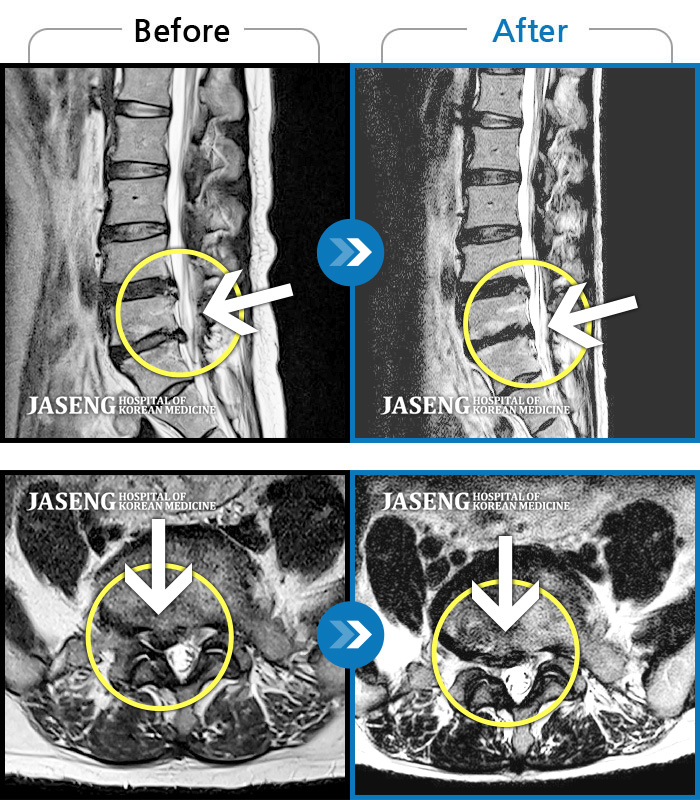

허리디스크

천안 · 윤영웅 원장

허리, 둔부 및 다리로 통증과 저림이 심해서 옆으로 잘 수 없어요.

촬영시기

2021.04.05 ~ 2022.03.25

2022.03.25